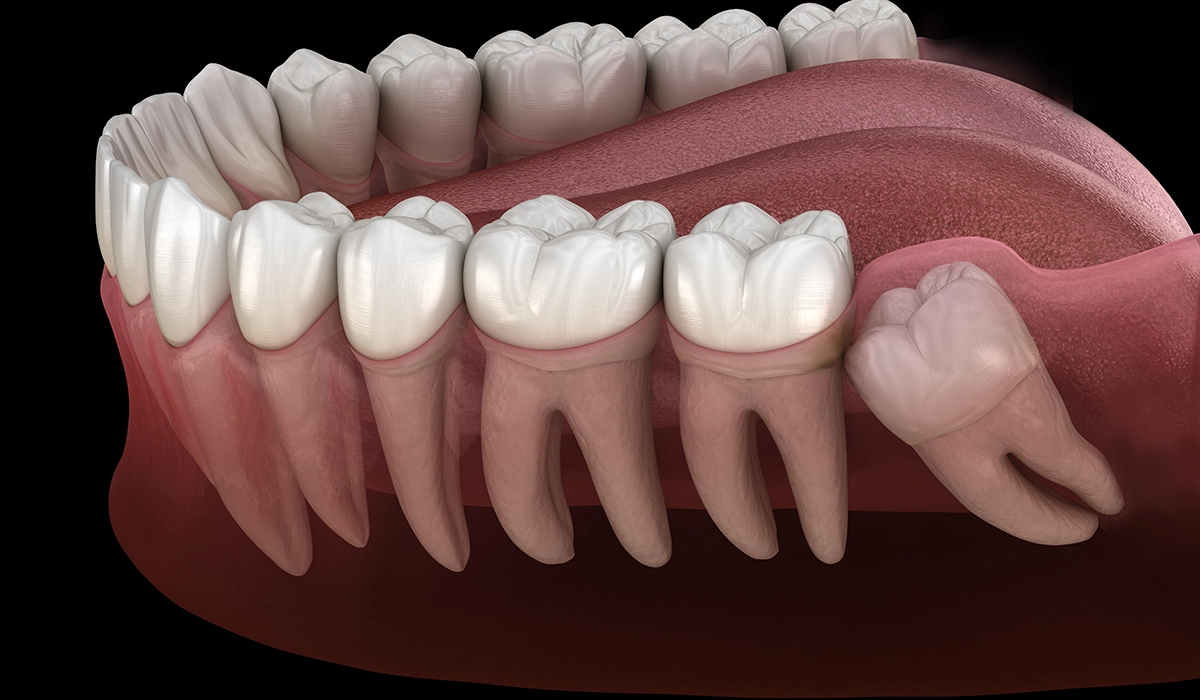

親知らずとは「智歯」や「第3大臼歯」とも呼ばれる歯で、20歳前後で生えてくることが一般的です。親知らずは通常上下左右4本ありますが、全ての親知らずが生えてくるかはわかりません。また、生えてきたとしても斜めに生えてきたり、半分だけ生えたりすることも多いのです。

親知らずがまっすぐ生えていない場合、他の歯に負担がかかっている場合があります。具体的には、隣の歯を圧迫しているケースです。この場合、圧迫されている歯が動きにくくなってしまい矯正治療の進行に影響が出てしまうこともあります。

また、親知らずが隣の歯に強く当たっている場合、隣の歯の根っこが吸収されて短くなってしまうこともあります。

親知らずが斜めに生えていると、歯を動かしにくくなったり、他の歯に圧力がかかることで治療中に予期せぬ歯の移動を引き起こしてしまうこともあります。

さらに、矯正後に親知らずが他の歯を押し出して後戻りの原因になることもあります。治療をスムーズに進めるために親知らずの抜歯が推奨されることもあります。